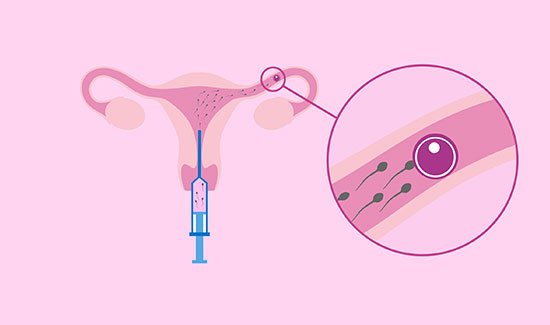

Artificial Insemination Homologous

Artificial Insemination Donor Super Ovulation and Intra Uterine Insemination